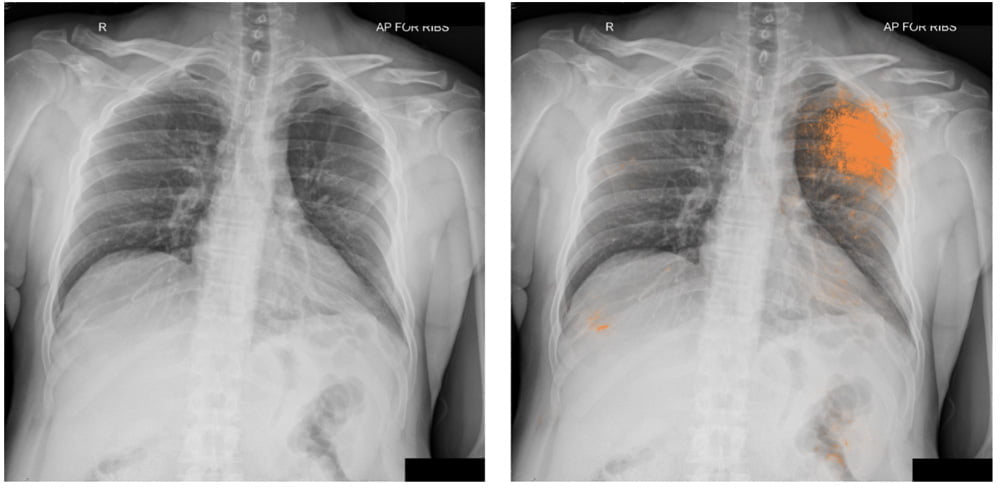

Neue Google-KIs können Röntgenaufnahmen von Lungen auf Krankheiten analysieren. Sie erreichen bei ihren Diagnosen das Niveau von Radiologen.

Künstliche Intelligenz breitet sich rasant in der Medizin aus: Auf Bildanalyse trainierte KIs identifizieren Brustkrebs, Lungenkrebs oder Hautkrankheiten. Google stellt jetzt neue KI-Systeme vor, die zu Röntgenaufnahmen der Lunge Diagnosen stellen können.

Nach dem Training konnten die spezialisierten KIs vier Diagnosen stellen: Pneumothorax (kollabierte Lunge), Knoten und größere Massen, Frakturen und Materialansammlungen in der Lunge. Die KIs diagnostizieren laut Google auf dem Niveau menschlicher Radiologen.

Das gilt für korrekte Diagnosen ebenso wie für Fehldiagnosen: Die KIs identifizierten oft Befunde, die von Radiologen übersehen wurden und umgekehrt. Die Fehldiagnosen der Radiologen sind menschliches Versagen, die der KI sind durch Datenlücken zu erklären. Google sieht die Zukunft des KI-Einsatzes in der Medizin in der Zusammenarbeit zwischen Mensch und Maschine.